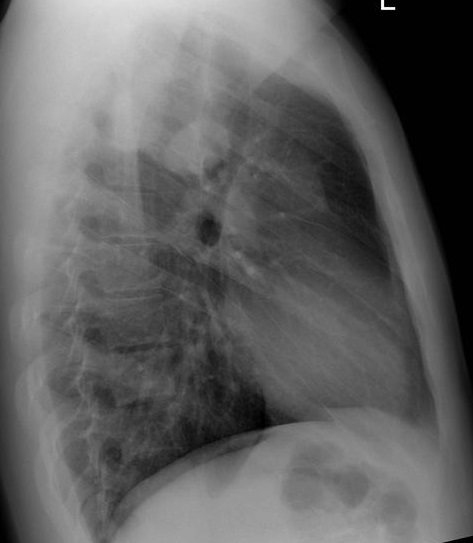

Image radiologique plain film et TDM : Aspect

radiologique plain film et TDM sur les côte du thorax est

image de destruction osseuse, permeative excentree et infiltrer

avec de bord irrégulier, Les couches de

réaction périostées créant

l'image d'une coque corticale en pelure d'oignon

,

Plus rarement, la lésion peut être avoir un caractère mixte,

c'est-à-dire lytique et sclérotique

.